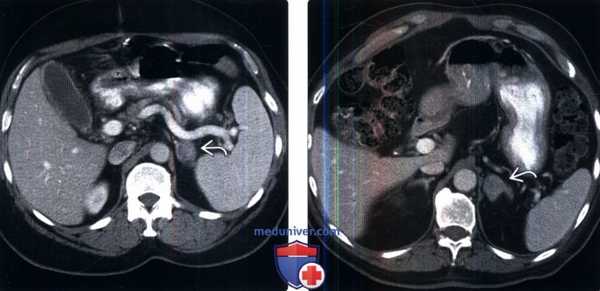

(Слева) КТ с контрастированием, аксиальная проекция: у пациента, страдающего раком толстой кишки, выявлены гладкие однородные метастазы в надпочечнике слева. Вне клинического контекста статистически более вероятна аденома, однако история заболевания, метастазы в печени (не показаны) и рост опухоли указывают на метастазы.

(Справа) КТ с контрастированием, аксиальная проекция: у пациента с раком легкого в анамнезе выявлено новое изолированное образование надпочечника. Несмотря на то, что относительное вымывание, составляющее 42%, может указывать на аденому с низким содержанием липидов, адреналэктомия, проведенная с учетом отсутствия других поражений, подтвердила метастаз.е) Диагностическая памятка: